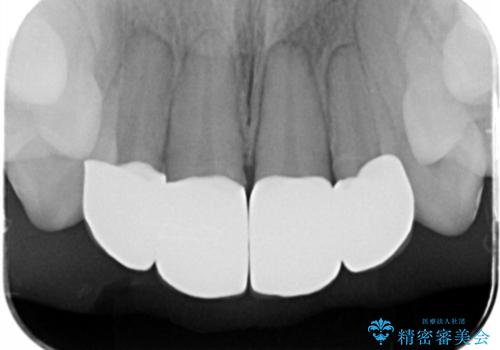

- 仮歯のまま放置してしまい、変色を改善しきれいなセラミッククラウンをいれたい、と希望され来院されました。

特に虫歯の再発や神経の症状等問題を認めなかったので、審美的に優れるセラミッククラウンに仮歯を置き換えていきます。